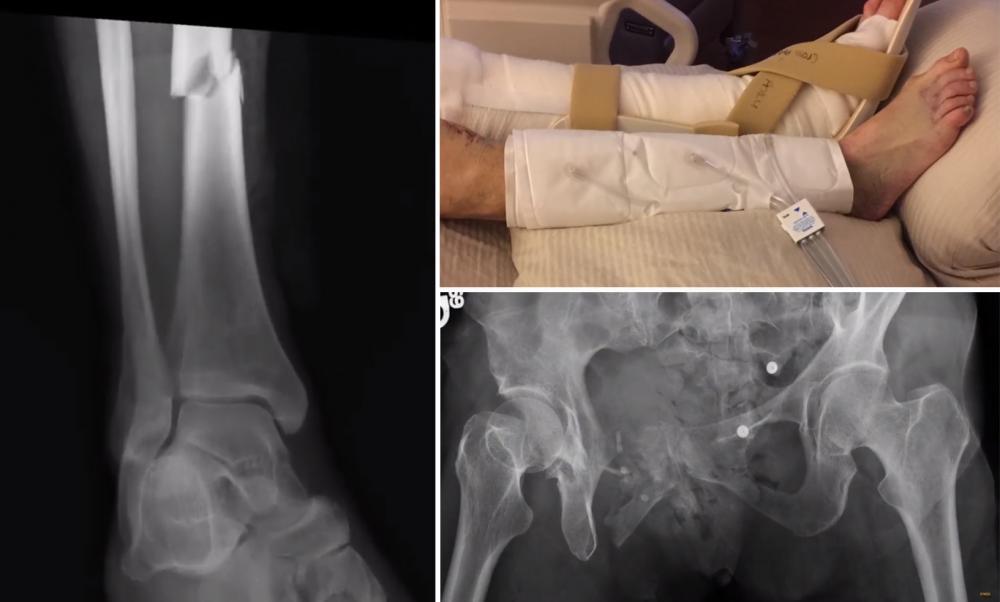

X ray of broken leg and pelvis.

Left and bottom: X-ray images show the broken leg and pelvis that Joyce Johnson suffered after being thrown from a bike trolley in 2015. Top, Johnson's legs as she healed at VCU Medical Center. (Photos courtesy of Joyce and Rich Johnson)